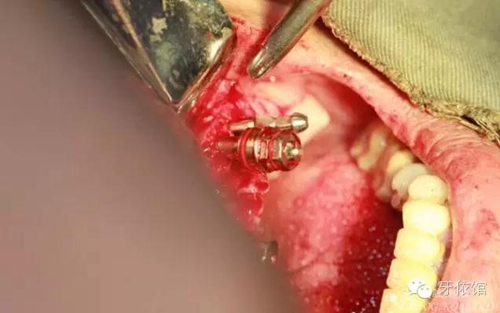

其余牙位也分別將植體植入

去除多余軟組織

將攜帶體重新與植體連接

將左側(cè)5(5個(gè)月前種的)連接轉(zhuǎn)移桿